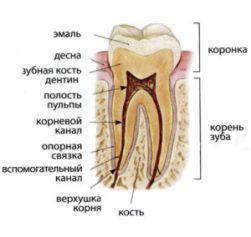

Эндодонтия – наука о методах и приемах, которые используют при лечении корневых каналов зуба. Корневой канал – это пространство внутри зуба в котором находятся нервы и кровеносные сосуды. Корен ь зуба — сложный объект для лечения. Во первых, он недоступен визуальному контролю.во вторых, строение системы корневых каналов вариабельно, как по их количеству, так и по морфологии (строению). Как правило, многие каналы представляют собой «канальное дерево» и имеют разнообразные дельтовидные ответвления и щелевидные углубления, в которых находится пульпа зуба.

ь зуба — сложный объект для лечения. Во первых, он недоступен визуальному контролю.во вторых, строение системы корневых каналов вариабельно, как по их количеству, так и по морфологии (строению). Как правило, многие каналы представляют собой «канальное дерево» и имеют разнообразные дельтовидные ответвления и щелевидные углубления, в которых находится пульпа зуба.

Перед началом эндодонтического лечения проводится рентгенологическое обследование, которое позволяет изучить анатомические особенности (количество и конфигурацию корней и каналов, размер и структуру пульпарной камеры), угол и радиус кривизны корневого канала, а также оценить стадию формирования корня, если пациент подросток. Если зуб ранее лечен эндодонтически, то такое обследование позволяет выявить перфорацию корня, наличие отломков эндодонтического инструмента в корневых каналах, оценить степень обтурации корневых каналов, обнаружить изменения в костной ткани, окружающей зуб.

В процессе эндолечения на отдельных этапах применяется апекс-локатор для измерения рабочей длины корневых каналов. После пломбировки коревых каналов проводится рентгеновский контроль качества обтурации.

Хорошим подспорьем врачу-эндодонту служит бинокулярная лупа и операционный микроскоп. С их применением доктор безошибочно определит анатомическое строение корневых каналов, например, наличие ответвлений и устьев, кальцификацию каналов. Благодаря хорошему освещению в операционный микроскоп хорошо видны детали участков корня, вплоть до самой его верхушки.